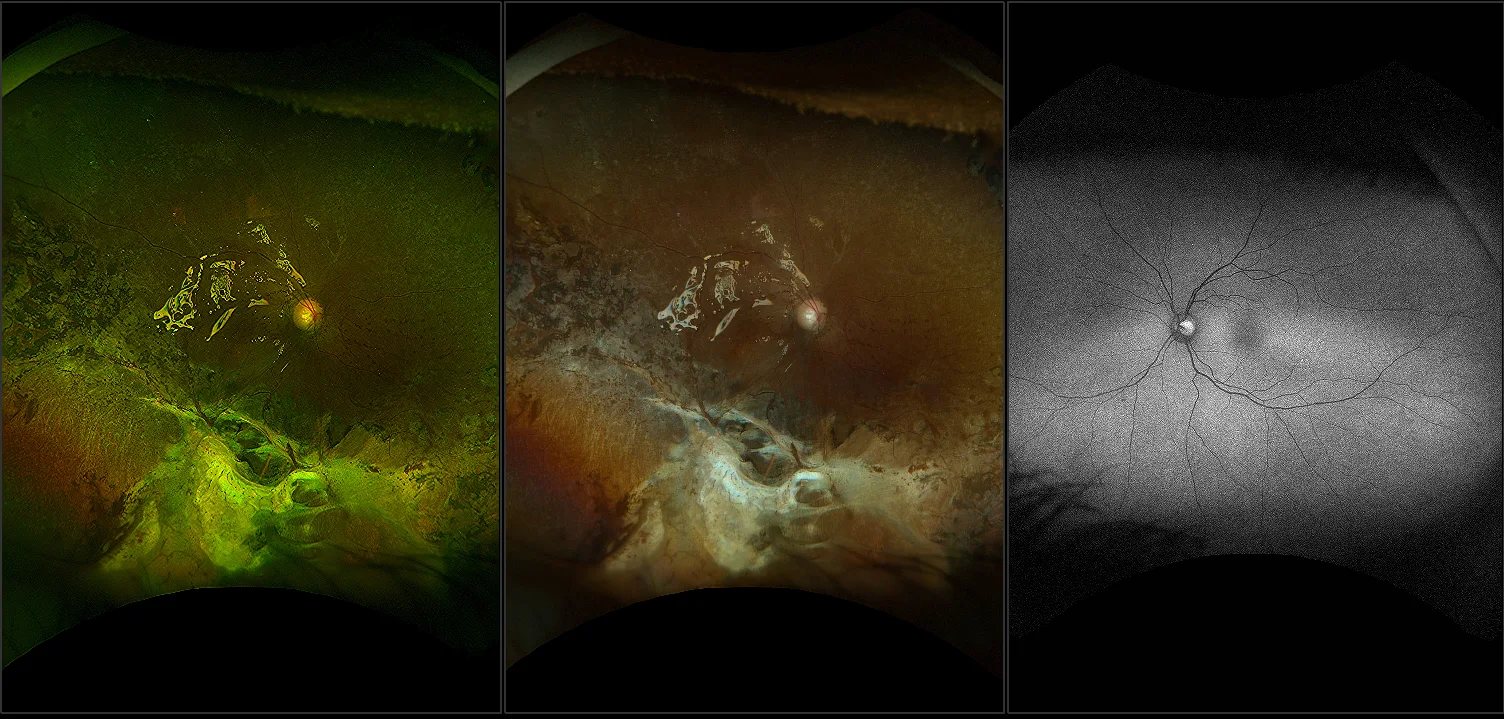

California - Lattice Degeneration - Montage, RG, RGB